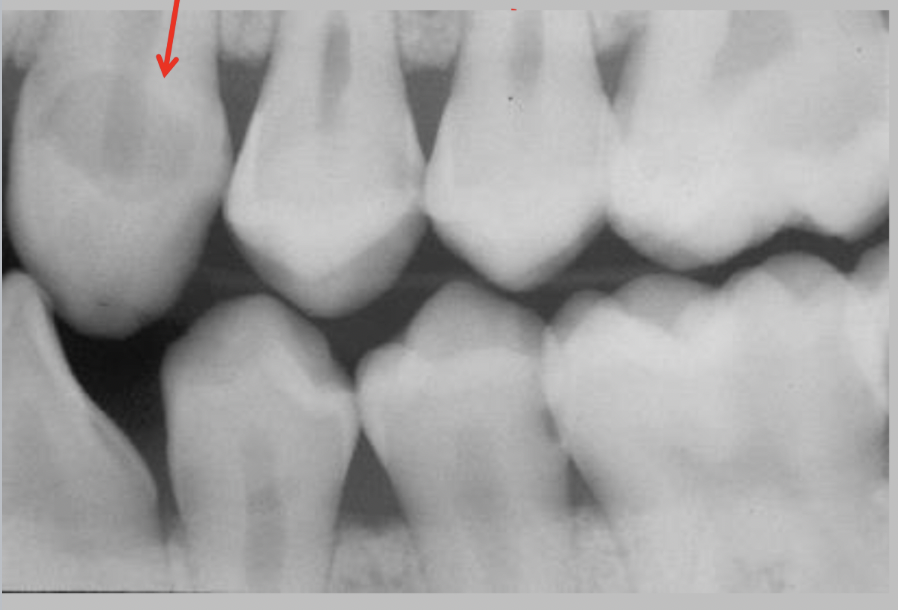

3

A

Initial caries (IC)